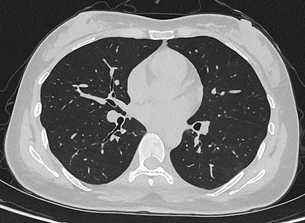

目前,华西厦门医院已基于该设备完成第一批患者扫描。“光子计数能谱CT的临床落地,是我国创新能力的重要体现,真正实现了对国外 ‘卡脖子’技术的突破。光子计数能谱CT实现了辐射剂量大幅降低,让患者CT扫描更安全。我们在临床案例中看到,设备不仅低剂量且高清,肺结节依然清晰可辨,临床价值十分突出。设备将在华西厦门医院的全链条、全生命周期的健康管理服务中发挥重要作用。” 华西厦门医院党委书记廖志林说。

联影uCT Ultima扫描的0.2mm肺部超高清成像,扫描剂量低至0.1mSv